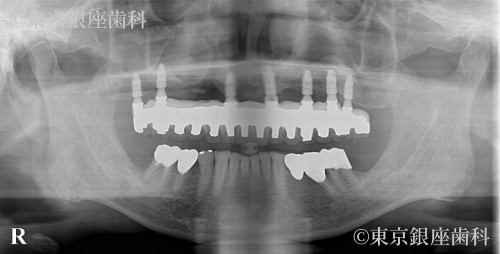

複数回の再埋入を経て骨と結合しづらい体質を克服した70歳代男性のインプラント症例

After

骨と結合しづらい体質でインプラントが抜けることが続いたが、材料変更(HAコーティング等)で改善。2年半かけ安定した状態に。

上顎ワンデイインプラント+骨造成+サイナスリフト

腫れ・痛み・出血、結合不全、副鼻腔炎、再手術の可能性